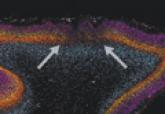

Credit: Virginia Tech A novel technique that can detect the subcellular location of a protein may help improve the study of therapies for cancer...